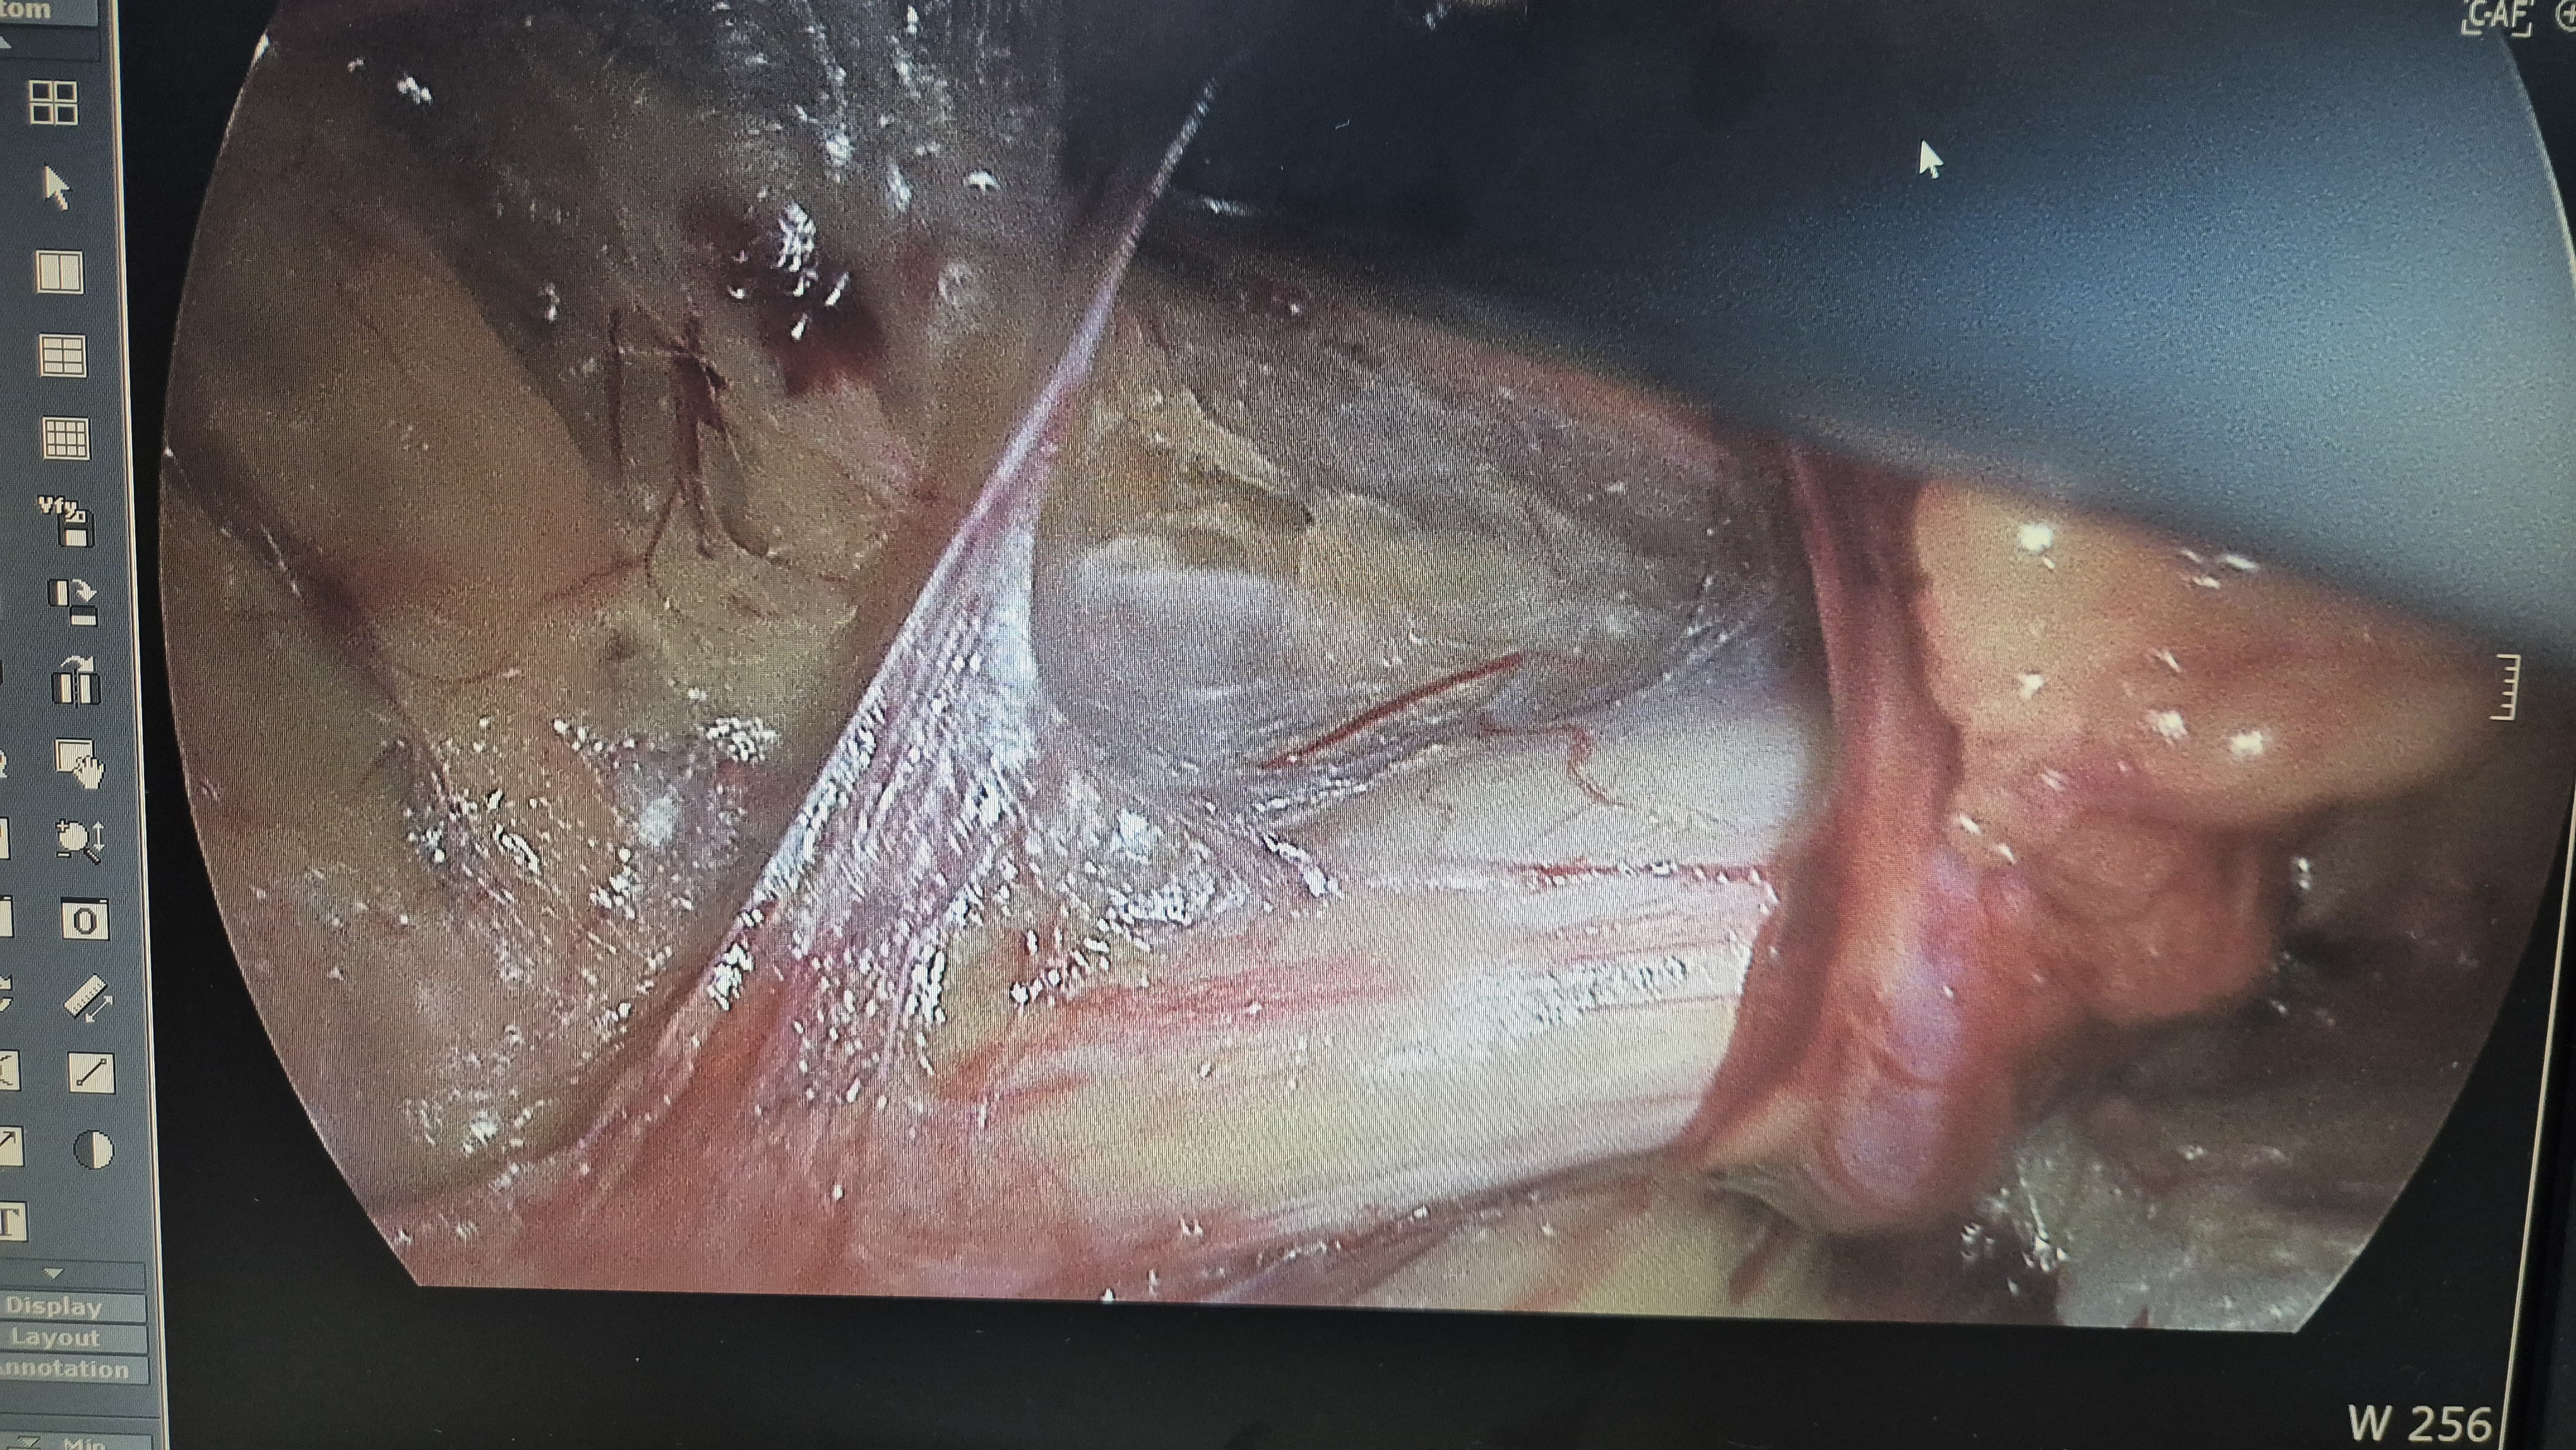

좌측 서혜부 종물 주소로 내원하여 초음파 시행후 서혜부 탈장으로 확인되어,

방금 복강경 탈장교정술을 시행했습니다.

탈장 확인후 박리.

메쉬로 고정.

수술은 15분 걸렸습니다.